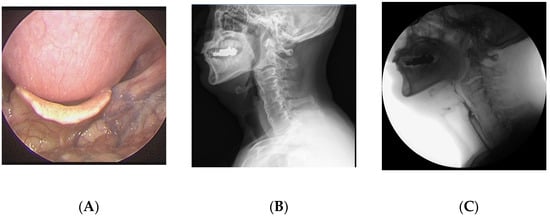

A 64-year-old man visited the department of otolaryngology presenting with swallowing difficulty for the past 2 months. Although he was able to have an oral diet, he felt difficulty in swallowing solid food and showed severe aspiration tendency in swallowing liquid food. His medical history included atrial fibrillation and he was on digoxin. On laryngoscopic examination, a large protruding mass was identified in the posterior pharyngeal wall (Figure 1). Lateral cervical radiography and computed tomography (CT) revealed continuous irregular hyperostosis along the anterior aspect of the cervical and upper thoracic vertebral bodies, suggesting DISH with a beak-shaped osteophyte compressing the posterior pharynx. Preoperative visual fluoroscopic swallowing study (VFSS) revealed moderate dysphagia in the oral and pharyngeal phases with incomplete closure of the epiglottis. For solid food, a small amount (<10%) of residue was demonstrated. For liquid, direct aspiration to the trachea was identified. He was referred to the spine center for surgical removal of the osteophyte, which was causing dysphagia. After conventional transverse anterolateral skin incision, the osteophyte was removed via the modified Smith–Robinson approach. The osteophyte was using osteotomes starting from the groove between the vertebral body and the osteophyte. The surgery took 60 min, and blood loss was less than 50 mL. Bone wax was applied to the bony margin after osteophyte removal for hemostasis as well as preventing recurrent osteophytes. His symptoms markedly improved immediately after the surgery. He felt no discomfort swallowing solid or liquid food. Postoperative laryngoscopy showed the disappearance of the mass lesion at the pharyngeal wall and widening of the pharyngeal space. There was no evidence of osteophytes at 1-year postoperative follow-up.

Figure 1.

A 64-year-old man presented with swallowing difficulty for the past 2 months. (A) Preoperative laryngoscopy revealed a huge protruding mass at the posterior pharyngeal wall. (B) Lateral cervical radiograph showed continuous irregular hyperostosis along the anterior aspect of the cervical and upper thoracic vertebral bodies, suggesting diffuse idiopathic skeletal hyperostosis (DISH), with a beak-shaped osteophyte compressing the posterior pharynx. (C) Preoperative visual fluoroscopic swallowing study revealed moderate dysphagia in the oral and pharyngeal phases with incomplete closure of the epiglottis. (D) Postoperative laryngoscopy showed disappearance of the protruding mass at the posterior pharyngeal wall. (E) One-year postoperative radiograph showed no evidence of regrowth of the osteophyte.